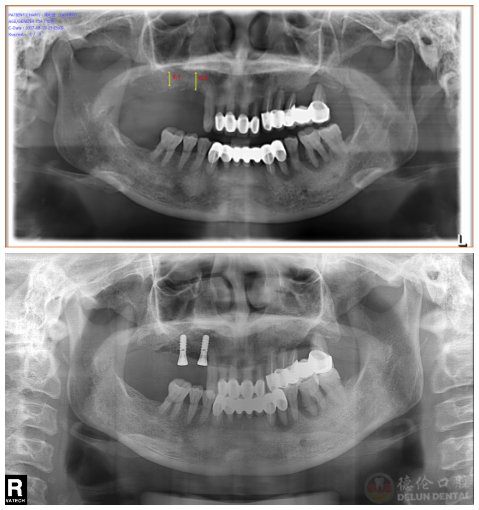

张阿姨手术前后对比照,于左上方种植2颗

今年54岁的张阿姨,右上后牙做烤瓷冠修复十余年,半年前烤瓷冠,随后却出现松动情况,影响进食,摘掉烤瓷冠后希望通过种植牙恢复咀嚼功能。

消毒、麻醉、微创切口、牙根植入……10分钟左右,第一颗新牙就“长”出来了

“两颗种植牙才用了20分钟,种完牙后没有不适感觉,当天就能吃东西,太神奇了!”现场引起了在观众的连连惊叹声。手术直播主角张阿姨下了手术台就立马回到直播现场,与现场观众分享种牙的感受,给现场想种牙又怕种牙的观众们吃了一颗“定心丸”,消除了大家的恐惧。